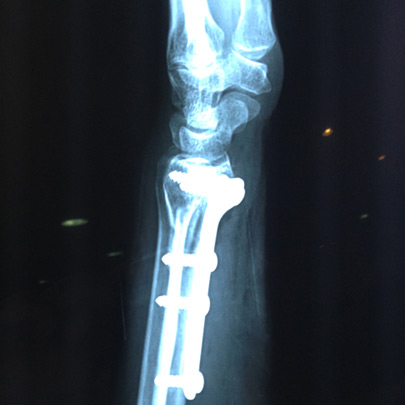

Fracturas y luxaciones

Tratamientos quirúrgicos